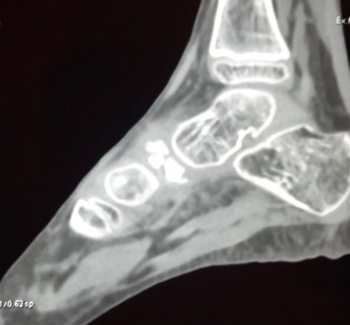

Il s´agit d´un patient de 17 ans, sans antécédents particuliers, consultant pour des douleurs du médio-pied droit depuis plusieurs années. Le scanner du pied met en évidence un aplatissement, une condensation, une fragmentation et une diminution antéropostérieure du naviculaire. La prise en charge est basée sur le repos et l´arrêt du sport avec port des semelles orthopédiques pour réduire les symptômes et traiter les problèmes de fond sur le long terme.